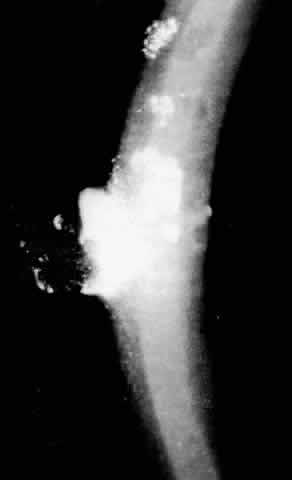

Slit lamp examination of young patients may only reveal small white or refractile anterior stromal spots in the central cornea. These spots often confused early investigators, leading some to misidentify this disorder as granular dystrophy. Later, the branching icicle-like lines (Fig. 7) appear in the anterior and then posterior stromal levels. The subepithelial location of many of these deposits lead to erosion of the overlying epithelium. Subepithelial scarring with destruction of Bowman's membrane then may take place allowing further opacification of the cornea and obscuration of the original lattice pattern. With further scarring, erosive episodes are less and corneal hypesthesia occurs.74 Other patients may have deeper stromal involvement, fewer epithelial erosions, and continued good vision until much later in life.

Fig. 7. Lattice dystrophy: typical branching filaments and similar irregular opacities.

Lattice corneal dystrophy has been subdivided into three subsets. Lattice dystrophy type 1, or classic lattice dystrophy as described above, has no systemic involvement, an early onset with fairly early reduction in visual acuity, and a history of multiple erosive episodes. Corneal lattice lines are centrally located, and the peripheral 1 to 3 mm of the cornea is usually clear.